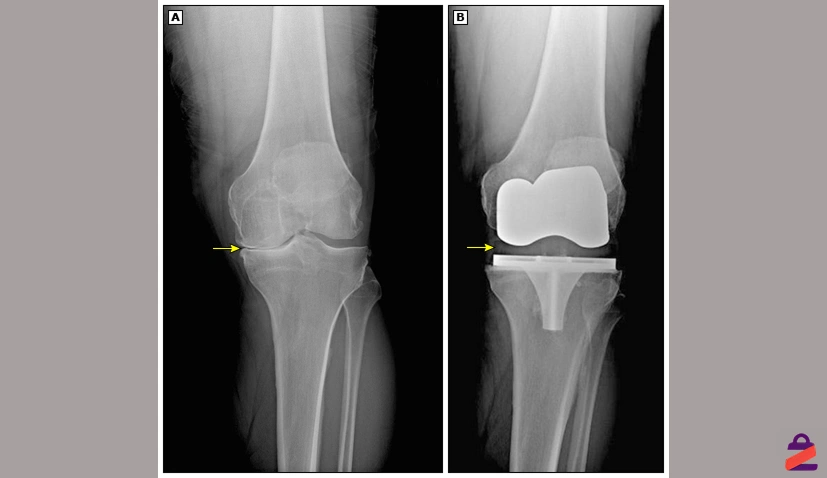

سپس بخشهای فرسودهی استخوان ران و استخوان درشتنی که سطح مفصل را تشکیل میدهند، با ابزارهای دقیق تراش داده میشوند تا سطحی یکنواخت و آماده برای قرار دادن قطعات مصنوعی ایجاد شود. در صورت نیاز، سطح زیر کشکک هم تراش داده میشود و با یک قطعه پلاستیکی جایگزین میشود.

بعد اجزای مفصل مصنوعی که معمولاً از فلز (مثل تیتانیوم یا آلیاژ کبالت-کروم) و پلاستیک فشرده ساخته شدهاند، با دقت روی استخوانها نصب میشوند.

این قطعات ممکن است با چسب مخصوص استخوانی در محل خود ثابت شوند. جراح پس از اطمینان از تراز بودن و حرکت روان مفصل، برش را بخیه زده و زانو پانسمان میشود.